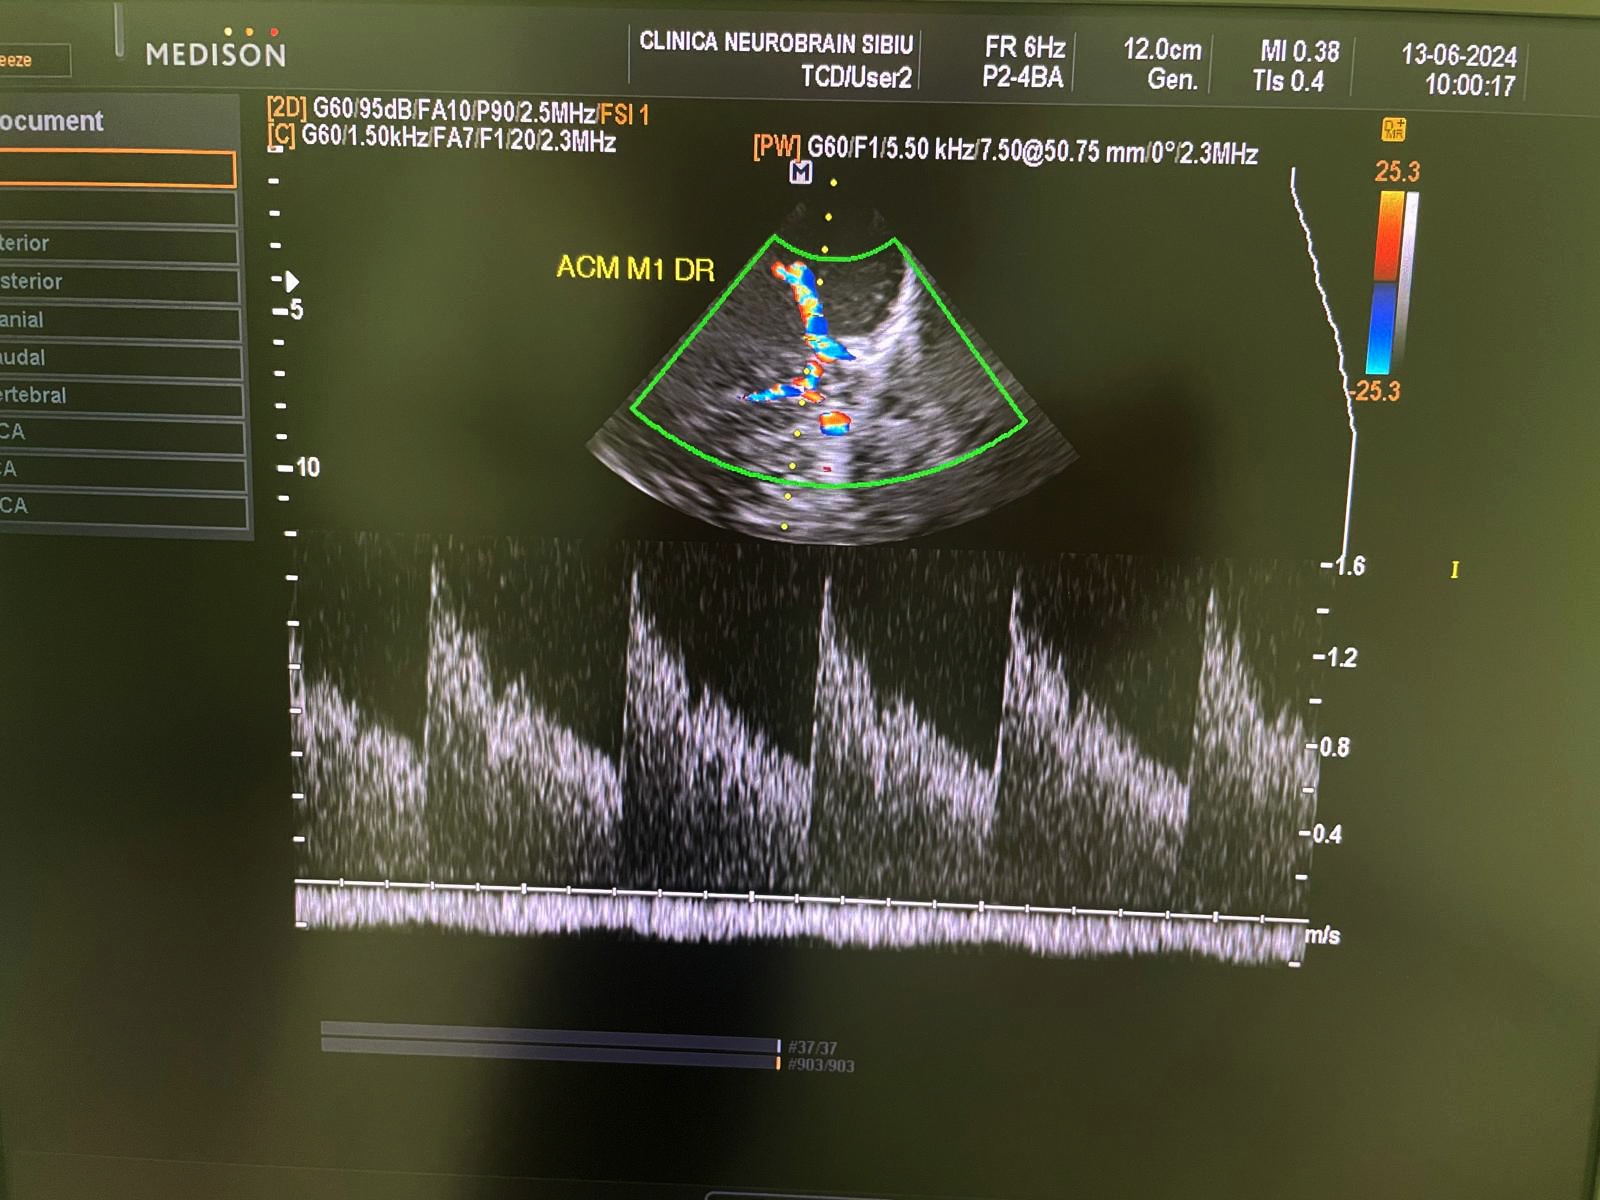

Ocluzia arterei carotide interne poate fi diagnosticată prin tehnici imagistice, cum ar fi ecografia Doppler, angiografia CT sau RMN-ul. Tratamentul poate include terapia cu anticoagulante, proceduri endovasculare pentru restabilirea fluxului sau, în cazuri grave, intervenții chirurgicale, cuendarterectomia carotidiană.

DR COSTEA SIMONA, medic specialist neurologie cu atestat de competență în Ecografie doppler artere carotide și vertebrale

și Ecografie doppler cerebrală